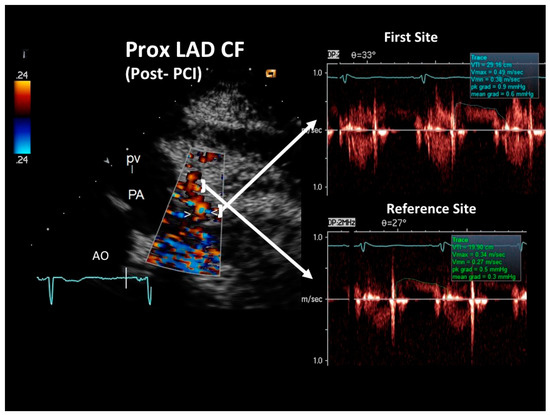

At the COVID intensive care unit, he was admitted to the catheterization laboratory, where he received immediate intravenous therapy, 5000 IU heparin sodium, 250 mg lysine acetylsalicylate and cangrelor bolus followed by continuous infusion (according to body weight). Coronary angiography showed sub-occlusive stenosis (lumen narrowing = 86%) of the proximal LAD (Figure 4), which was treated with balloon angioplasty followed by drug-eluting stent placement (Resolute Onyx 2.75 × 34 mm). Following the intervention, 0% residual stenosis was recorded, with an optimal residual flow and no dissection present (Figure 4). A total of 2 hours post-procedure, 180 mg oral ticagrelor (after the suspension of cangrelor) was administered, followed, from the following day, by 100 mg oral aspirin daily, 90 mg oral ticagrelor bis in die (as part of a dual antiplatelet regimen) and goal-directed medical therapy with a beta-blocker and highly intense statin therapy [19]. The ECG following PCI displayed persistent pseudo-normalization of T waves in the precordial leads; cardiac high-sensitivity troponin T (III assay) increased considerably to 3734 μg/L. Patient recovery was event-free, and he was transferred on the fourth day to the internal medicine department, pending the negativization of the SARS-CoV-2 molecular assay. He was discharged on the 7th day on dual antiplatelet therapy but not on anticoagulation therapy since his COVID infection had no thromboembolic complications [20]. After two months, he was re-evaluated by E-Doppler TTE, this time adding CFR assessment. The transtenotic velocity had dropped almost completely, indicating a patent stent (minimal residual stenosis at 26% of area reduction according to the continuity equation) (Figure 5), and the CFR was also normal (=3.3) (Figure 6), confirming the stent patency and complete recovery of microcirculatory function in the LAD myocardial territory.

Figure 5. Blood flow Doppler recording by E-Doppler TTE in the proximal LAD after stenting in the follow-up (same format as in the acute phase). Maximal velocity had dropped to 49 cm/s, yielding a residual stenosis area of 25% according to the continuity equation. The diastolic waves of the Doppler tracings are outlined in green, and the maximal velocity and time velocity integral are reported. Abbreviations as in Figure 2.